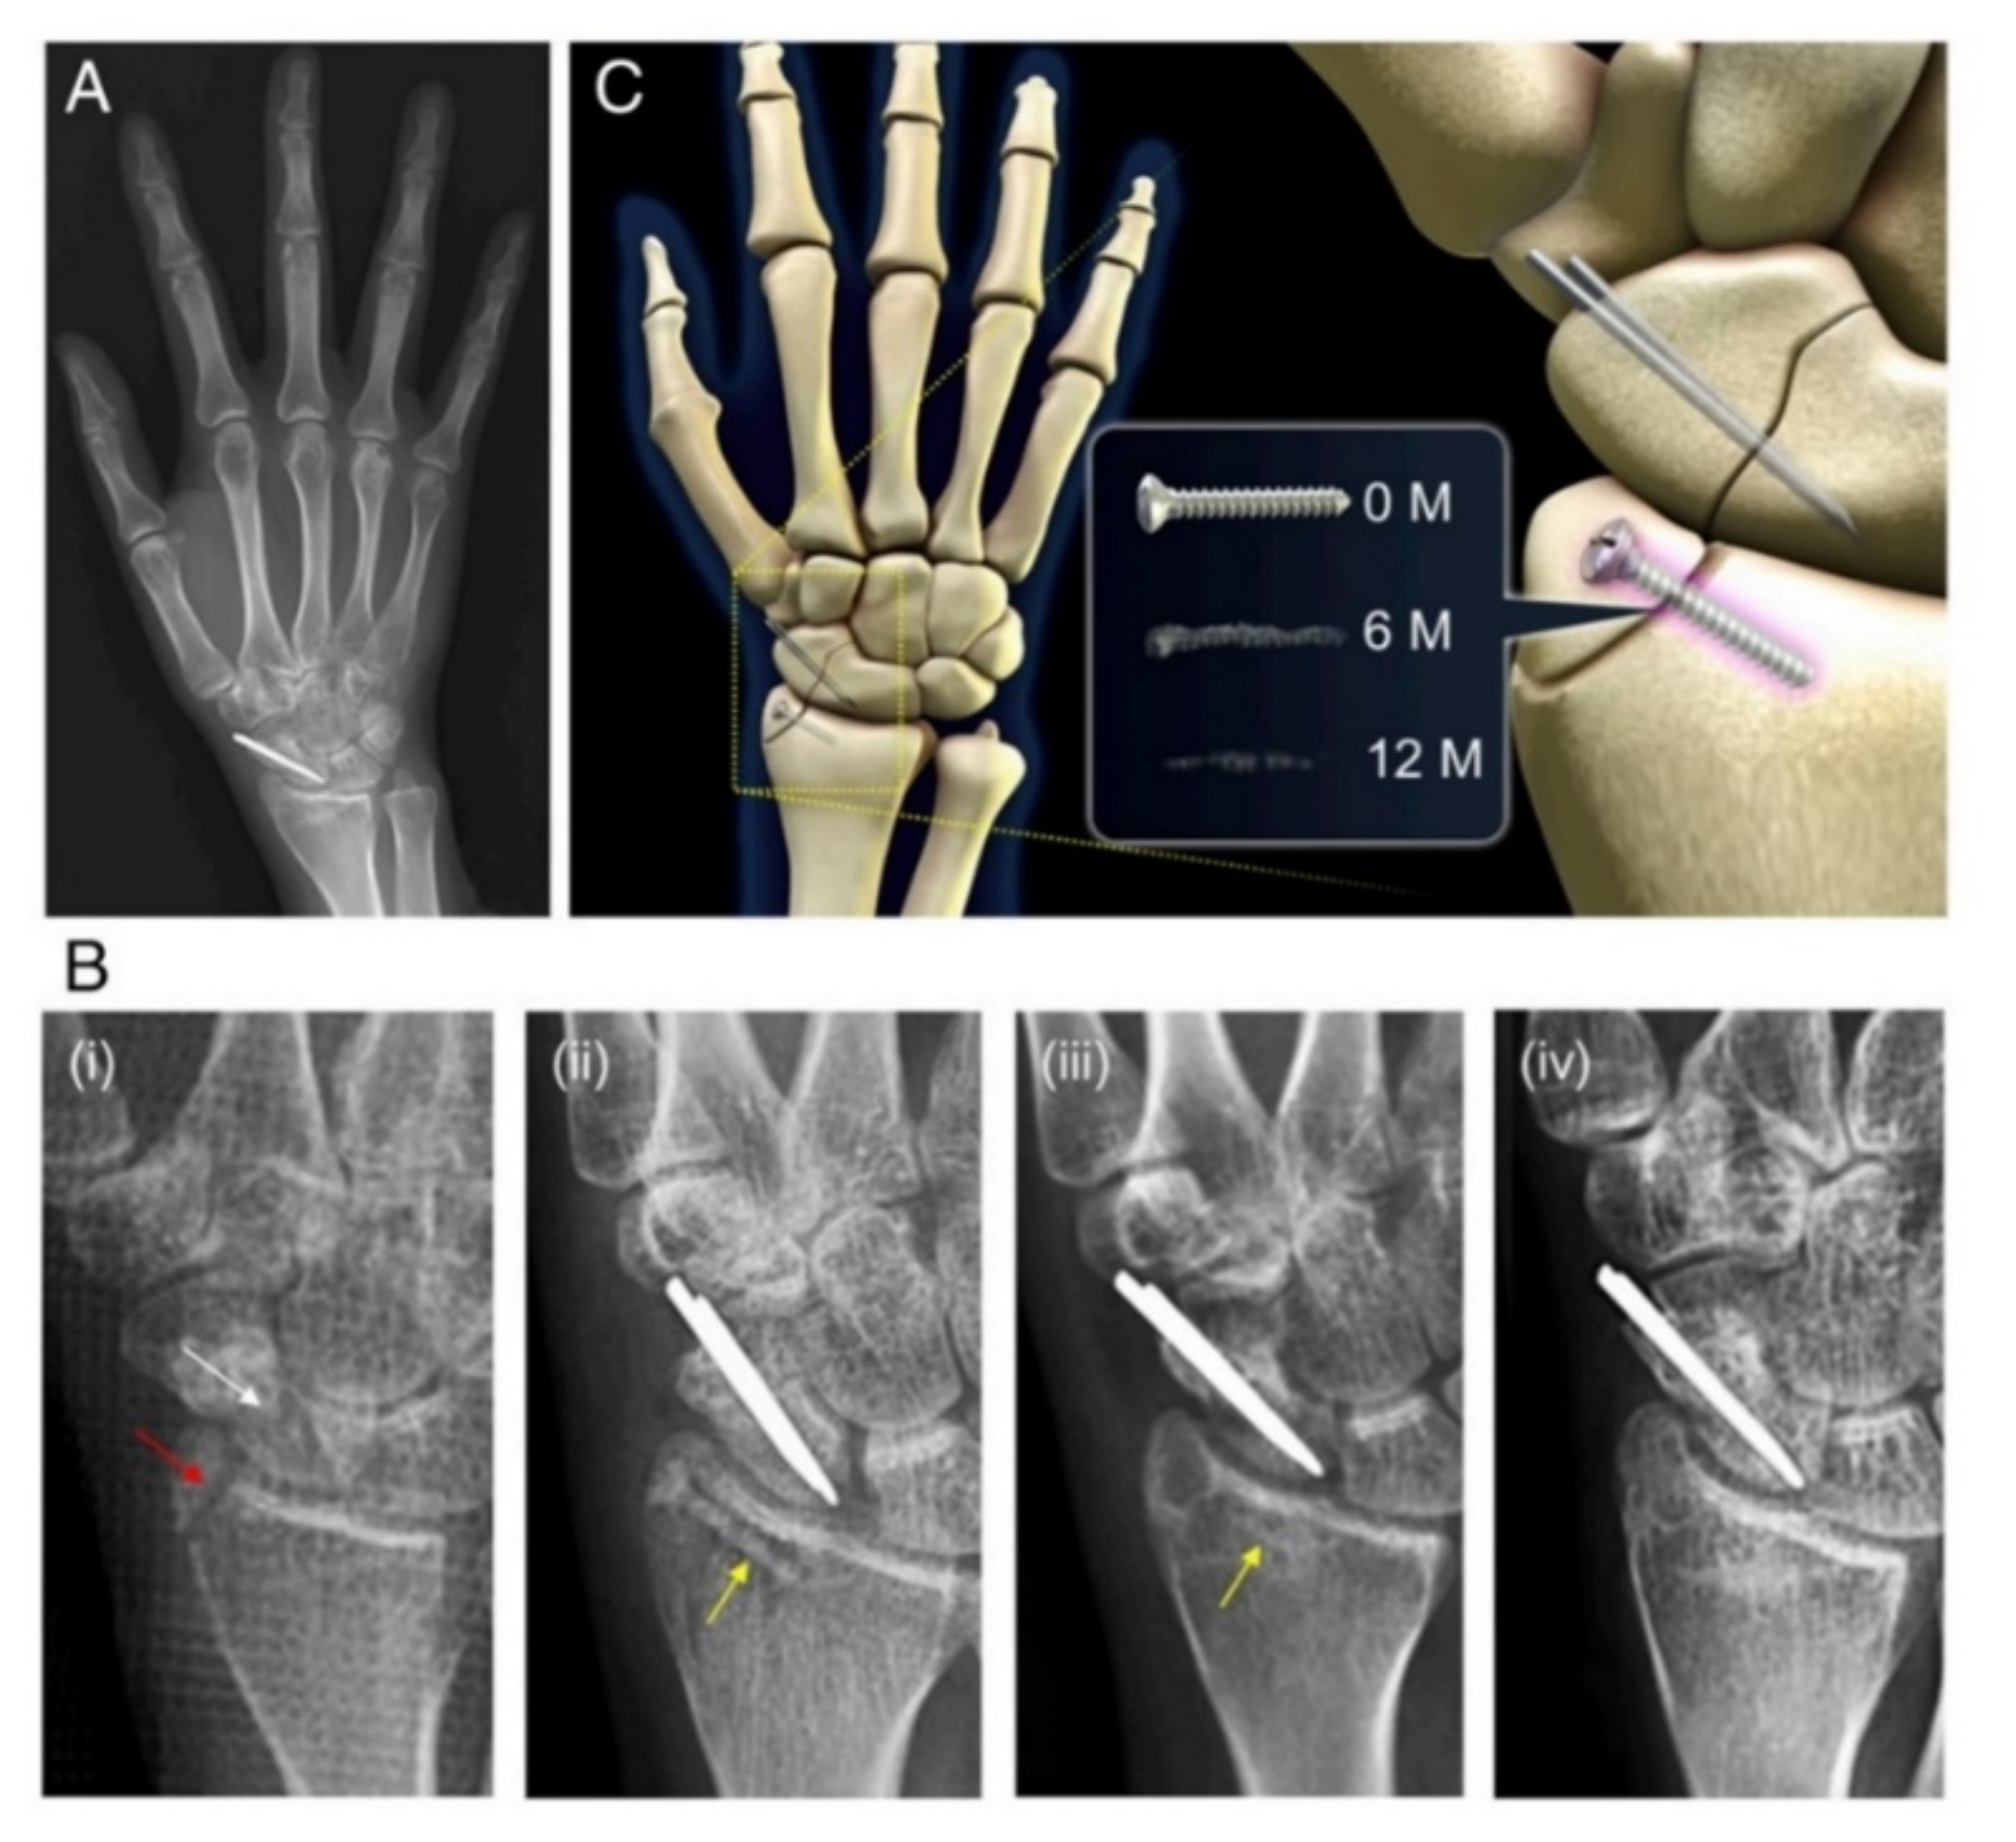

- Meier, R.; Panzica, M. First results with a resorbable MgYREZr compression screw in unstable scaphoid fractures show extensive bone cysts. Handchir. Mikrochir. Plast. Chir. 2017, 49, 37–41. [Google Scholar] [CrossRef]

- Turan, A.; Kati, Y.A.; Acar, B.; Kose, O. Magnesium Bioabsorbable Screw Fixation of Radial Styloid Fractures: Case Report. Jnl. Wrist Surg. 2020, 09, 150–155. [Google Scholar] [CrossRef]

| Scaphoid fracture | Magnesium-based headless Herbert screw | Mg-Y-RE-Zr/WE43 | Human (190 patients) | [27] |

| 5 | Excellent | 24 months | Extensive resorption cysts in the case of 3 patients | [147] | |